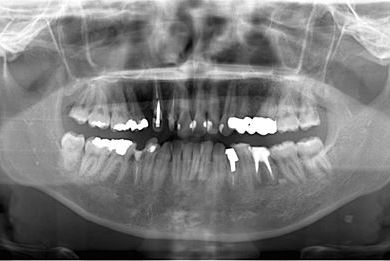

| 主訴 | 以前治療中のままだった部位の歯の根に膿が溜まって、痛みと腫れが出た。応急処置で切開して膿は取ってもらったが、根の治療がまだなので、お願いしたい。 | ||||||||||||||||||||||||||||||||

| 治療方針 | 抜歯と同時にインプラント埋入を行い、治療期間を短縮する。 | ||||||||||||||||||||||||||||||||

| 治療内容 | インプラント2本(抜歯即日スピードインプラント)、ハイブリッドセラミッククラウン3本 | ||||||||||||||||||||||||||||||||

| 総治療費 | 588,000円 | ||||||||||||||||||||||||||||||||

| 治療期間 | 8ヶ月 |